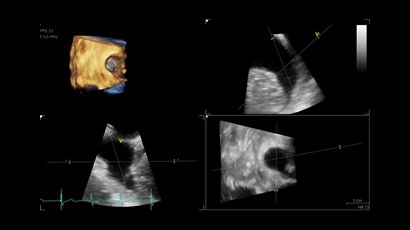

• Vivid IQ 4D с поддержкой технологии объемной реконструкции

4D:

Да

• 4D AUTO AVQ - модуль автоматического выравнивания, сегментации и обсчета размеров кольца аортального клапана по объемным данным.

• 4D AUTO LVQ - модуль расчета массы миокарда ЛЖ на основе данных 4D-исследования.